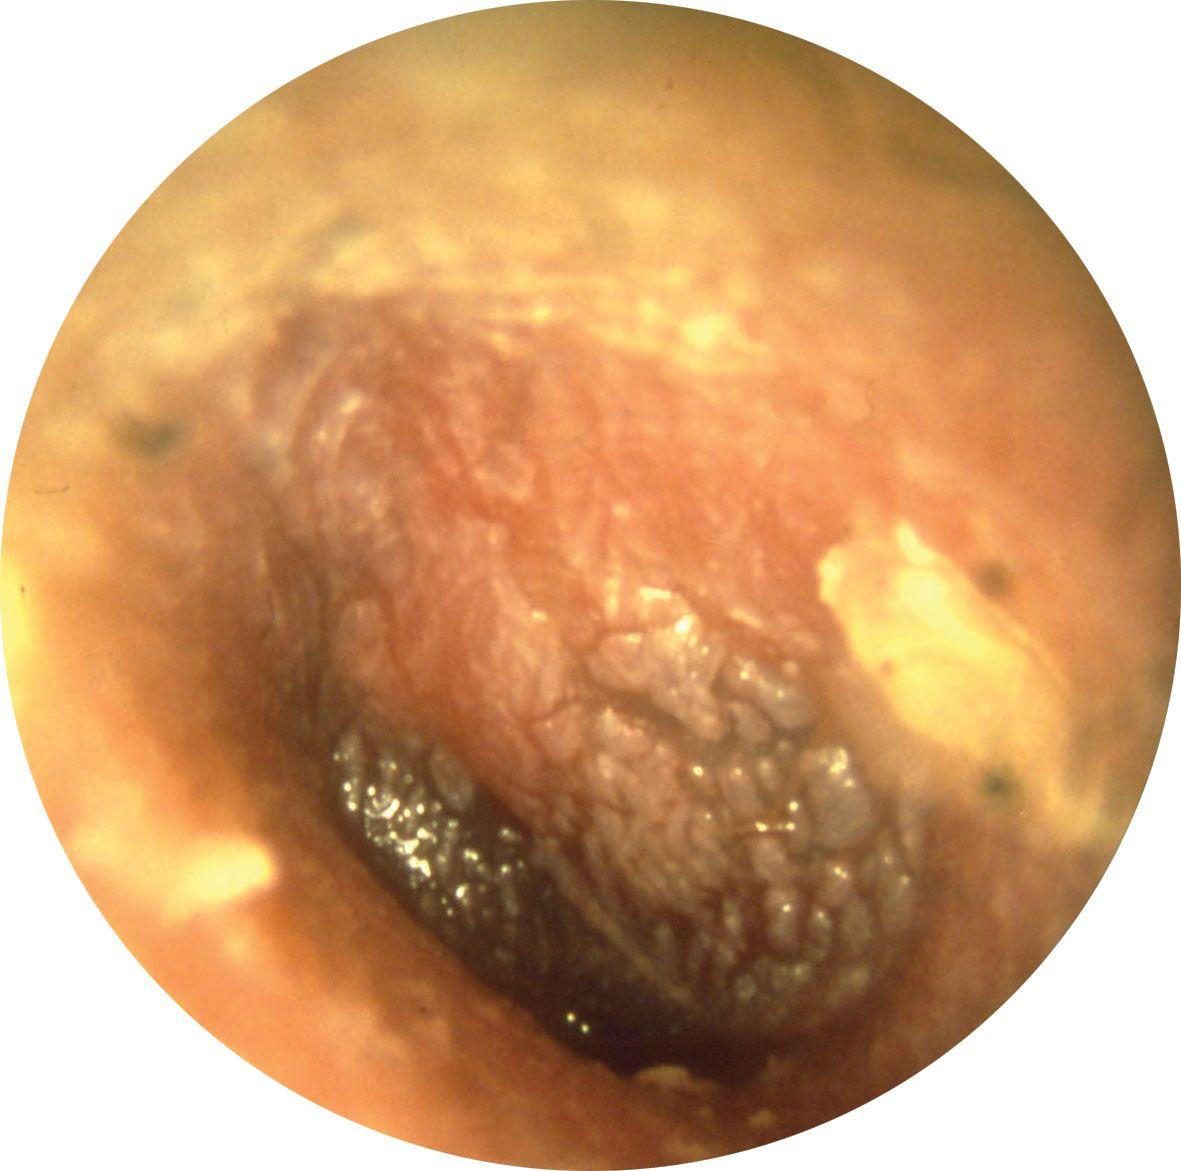

2.3 Viêm tai giữa mạn tính (giai đoạn nặng, có nguy cơ biến chứng)

Khi bệnh kéo dài mà không được điều trị đúng cách, hình ảnh viêm tai giữa ở người lớn trong giai đoạn này cho thấy tổn thương nghiêm trọng tại màng nhĩ và các cấu trúc tai giữa. Vi khuẩn có thể lan rộng, gây ra nhiều biến chứng nguy hiểm.

Dấu hiệu nhận biết qua hình ảnh

- Xuất hiện lỗ thủng trên màng nhĩ, có thể thấy dịch mủ chảy ra ngoài.

- Dịch mủ có màu vàng đậm hoặc xanh, đôi khi có mùi hôi do nhiễm khuẩn.

- Tổ chức xơ sẹo hoặc tổn thương tại khoang tai giữa, dấu hiệu của tình trạng viêm nhiễm kéo dài.

Triệu chứng lâm sàng

- Mất thính lực rõ rệt, gây khó khăn trong giao tiếp hằng ngày.

- Cảm giác đau tai âm ỉ, đôi khi lan ra thái dương hoặc cổ.

- Chóng mặt, mất thăng bằng nếu viêm nhiễm lan sang tai trong.

Giai đoạn này đòi hỏi cách chữa viêm tai giữa chuyên sâu, có thể cần can thiệp phẫu thuật để bảo tồn thính lực và ngăn ngừa biến chứng nguy hiểm như viêm màng não hoặc áp xe não.